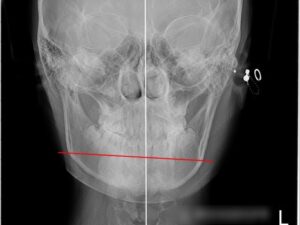

반갑습니다, 면목역 치과 글로리의 김정은 대표원장입니다. 교정이 필요한 순간들이 꽤 여럿 있습니다. 가지런하지 못한 치열을 가졌을 때도 있고, 때로는 맞지 않은 교합 관계의 문제, 그리고 뻐드러진 치열을 가질…

치아는 우리에게 ✅ 식사를 할 수 있도록 저작의 기능을 가지며, ✅ 정확한 발음으로 말을 할 수 있도록 도와줍니다. ✅ 또한 얼굴의 형태와 대칭을 유지하는데 중요한 역할을 합니다. …